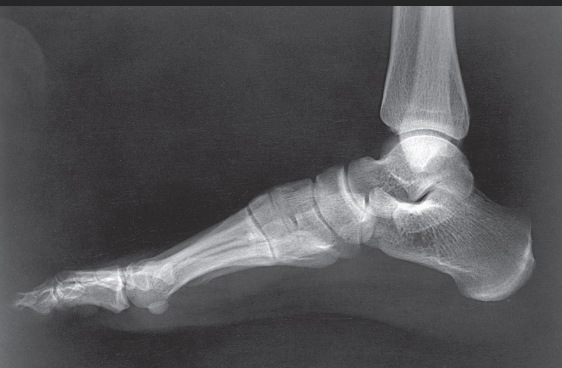

Name this projection.

AP oblique foot

Describe the position of the patient.

Seated or supine with their knee flexed and lower leg/foot rotated medially 30 degrees

Where does the CR enter?

Base of the 3rd metatarsal

What is demonstrated?

The lateral side of the foot from the toes to heel, the sinus tarsi, and the tuberosity of 5th metatarsal

The ________ metatarsals should be free of superimposition.

3rd-5th

Which metatarsals should be superimposed?

1st and 2nd

What could be done to demonstrate the opposite aspect of the foot?

Rotate the foot out laterally 30 degrees